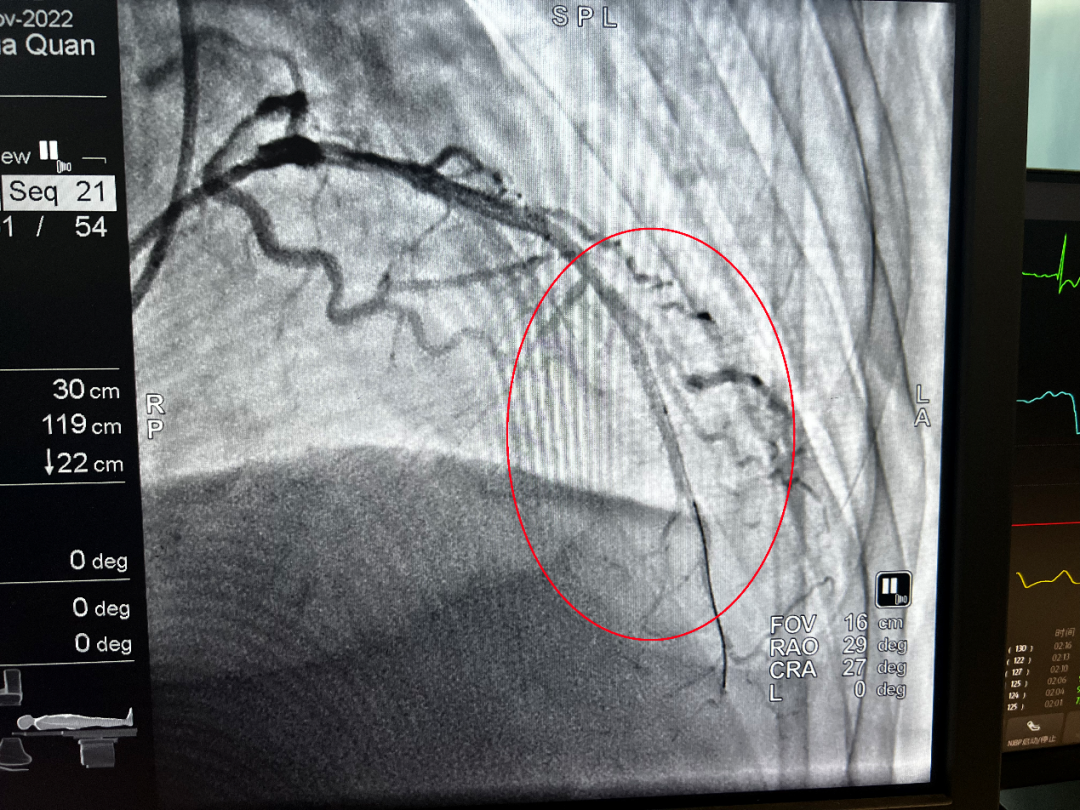

(介入后)

凌晨1點34分,導管室激活;1點38分,患者平車送入導管室;1點48分,穿刺成功;2點01分,導絲通過血管閉塞處……從王大爺首次醫(yī)療接觸到導絲通過,僅用時54分鐘。所有醫(yī)護人員繃緊神經(jīng),爭分奪秒,為患者開辟了一條脫離危險的綠色通道。術后,患者胸痛癥狀明顯緩解,轉危為安。